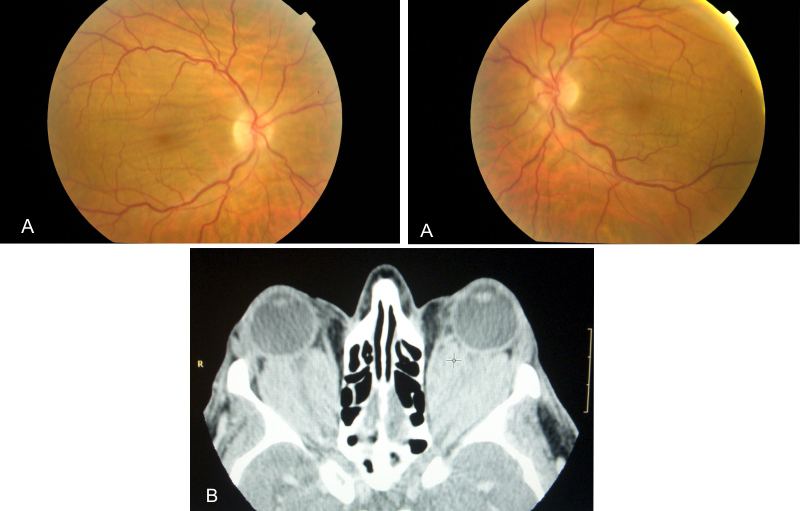

- Tumores orbitarios: los causan aquellas lesiones que ocupan el espacio peri o retrobulbar, en contacto con la parte posterior del globo ocular. Si son intraconales producen hipermetropía y ondulaciones radiales alrededor de la papila. Por el contrario, si son extraconales originan astigmatismo y pliegues concéntricos alrededor del nervio. Es preciso practicar pruebas de imagen si se sospecha esta causa, el tratamiento puede contribuir a la normalización del fondo de ojo (Figura 9 y Figura 10).

Figura 9. Fondo de ojo con de paciente que consultó por cambió refractivo unilateral (hipermetropía) y exoftalmos progresivo. Se aprecian pliegues oblicuos en el ojo izquierdo. El estudio de TC orbitario reveló una tumoración intraconal unilateral compatible tumor fibroso solitario de la órbita.

Figura 10. Enfermedad de Erdheim-Chester con ocupación orbitaria bilateral. Figura 10A. Fondo de ojo. Los pliegues coroideos asociados tienen una disposición horizontal y se localizan en la mácula. Figura 10B. TC orbitaria corte axial, se aprecia la ocupación del espacio intraconal por una lesión hiperdensa que aplana el polo posterior de ambos globos oculares.